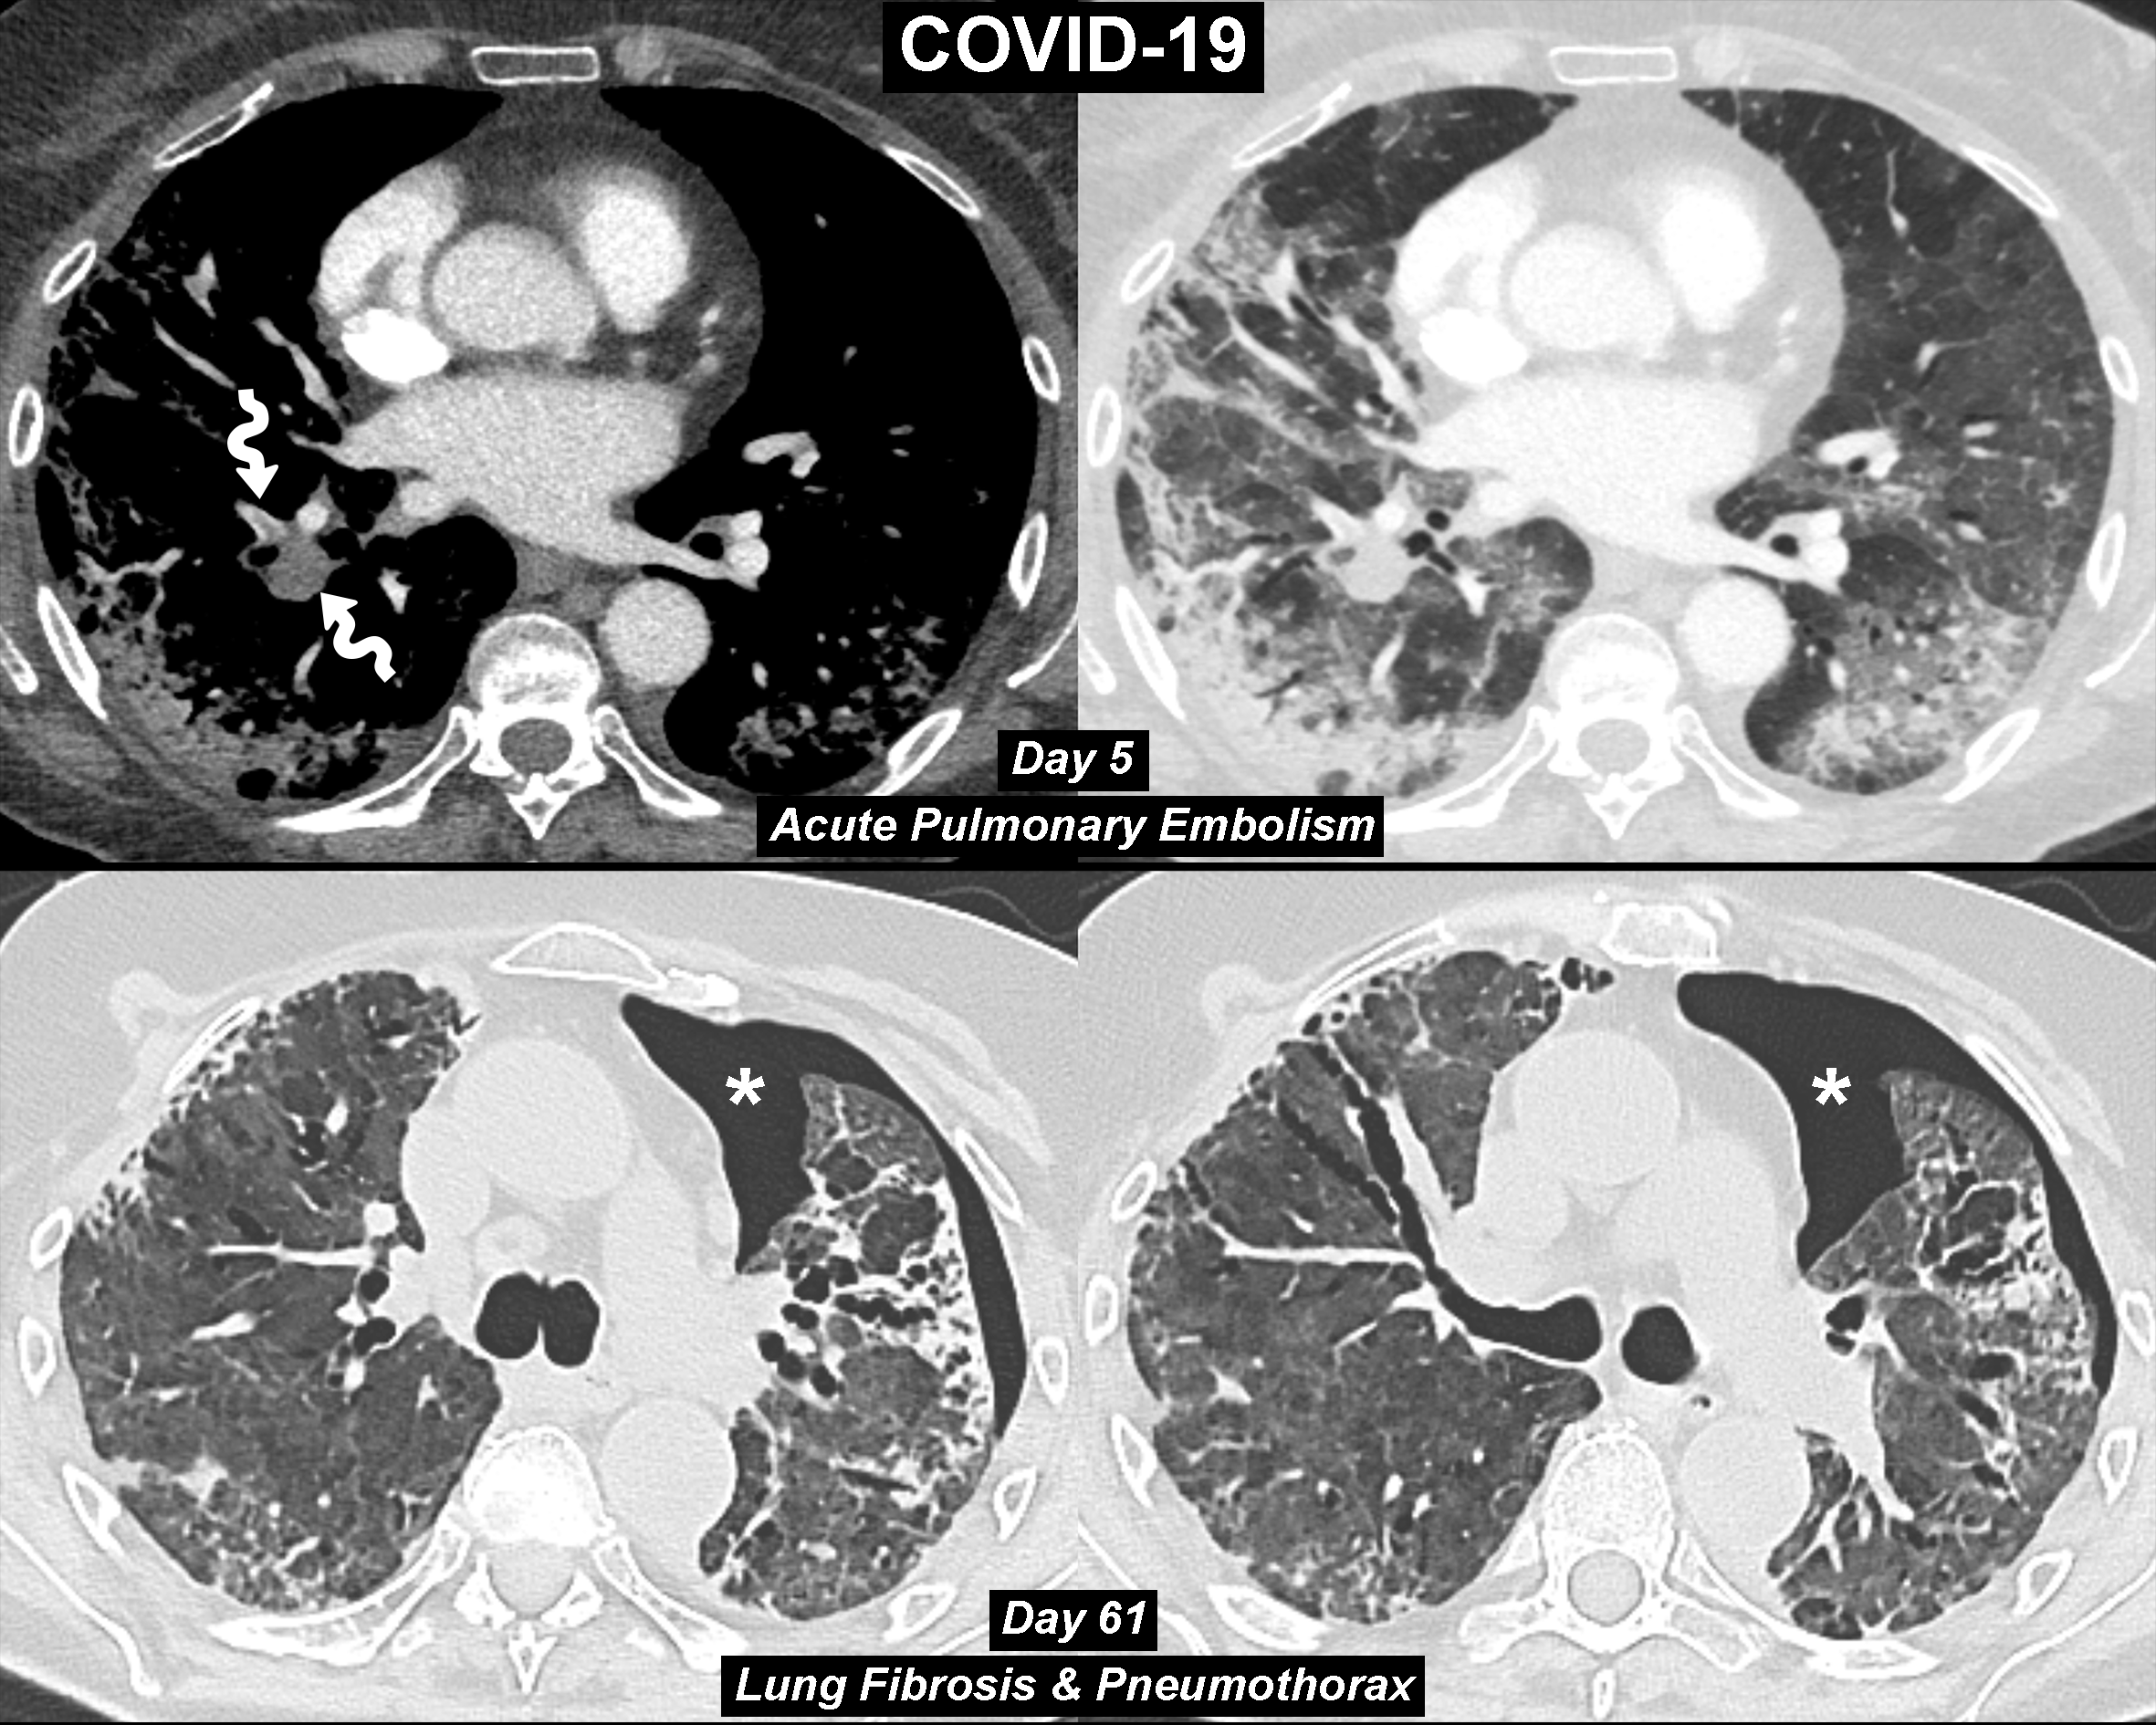

Diagnostics Free Full Text Covid 19 Pneumonia Three Thoracic Complications In The Same Patient Html

www.mdpi.com

Pulmonary Fibrosis In Critical Ill Patients Recovered From Covid 19 Pneumonia Preliminary Experience The American Journal Of Emergency Medicine

www.ajemjournal.com